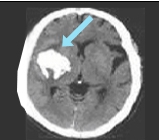

모야모야병은 뇌의 주요 혈관들이 점차 좁아지는 질병입니다. 이로 인해, 뇌에 필요한 혈액 공급이 제대로 이루어지지 않게 됩니다. 이런 현상을 보완하기 위해 뇌 내의 작은 혈관들이 활성화되어 더 많이 형성됩니다.

이 작은 혈관들의 형태가 연기처럼 흐르는 모양을 닮아 '모야모야'라는 이름이 붙여진 것입니다. 이 이름은 일본어에서 유래하였으며 연기가 구름처럼 피어오르는 모양을 뜻하는 말에서 비롯되었습니다.

뇌출혈

뇌출혈은 성인의 65% 미만과 어린이의 5%에서 발생하며, 어린이에 비해 성인에서 더 흔합니다.

주요 원인

약한 대체 혈관의 파열, 미세동맥류 또는 기타 동반된 혈관 기형이 원인으로 여겨집니다.

모야모야병은 뇌혈관조영술로 진단되며, 자세한 뇌혈류 검사 결과에 따라 치료가 진행됩니다.